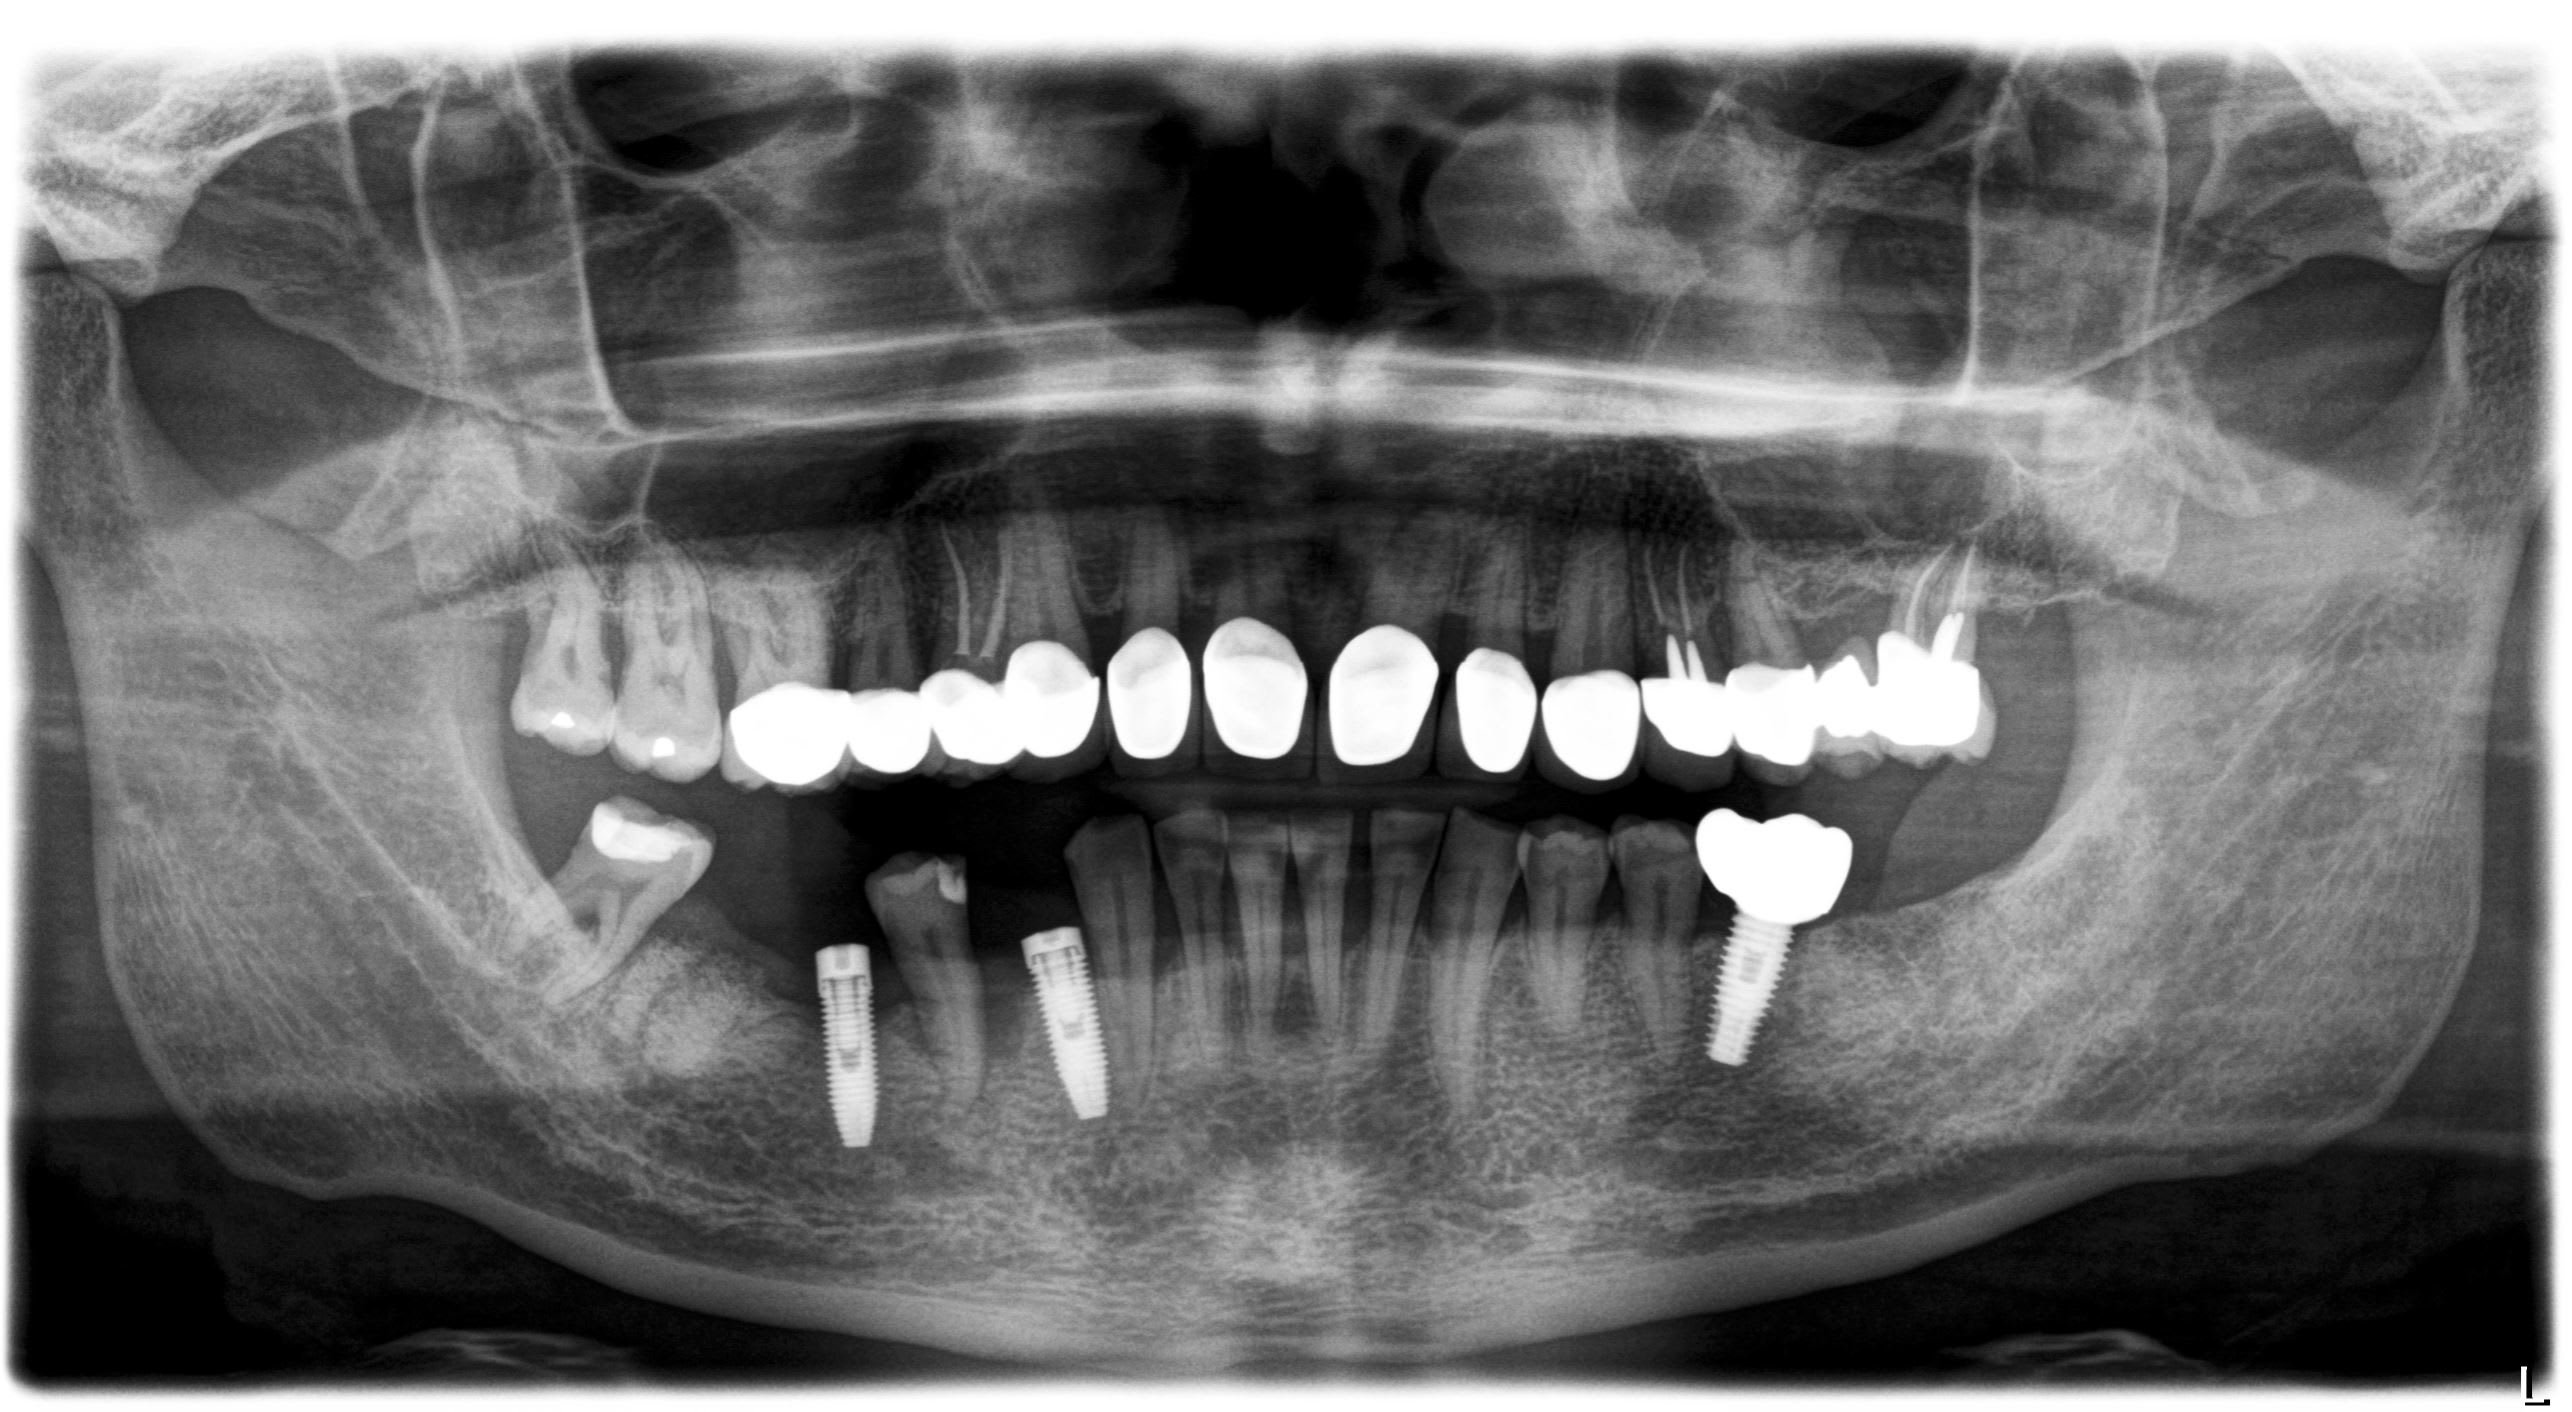

Hello, je recherche une âme charitable qui saurait me dire de quel type d'implant il s'agit, pour les 2 implants posés secteur 4. Marque/Modèle?

Pour l'axe/qualité pose, c'est un autre sujet ^^

Posés en IDF il y a 2/3ans